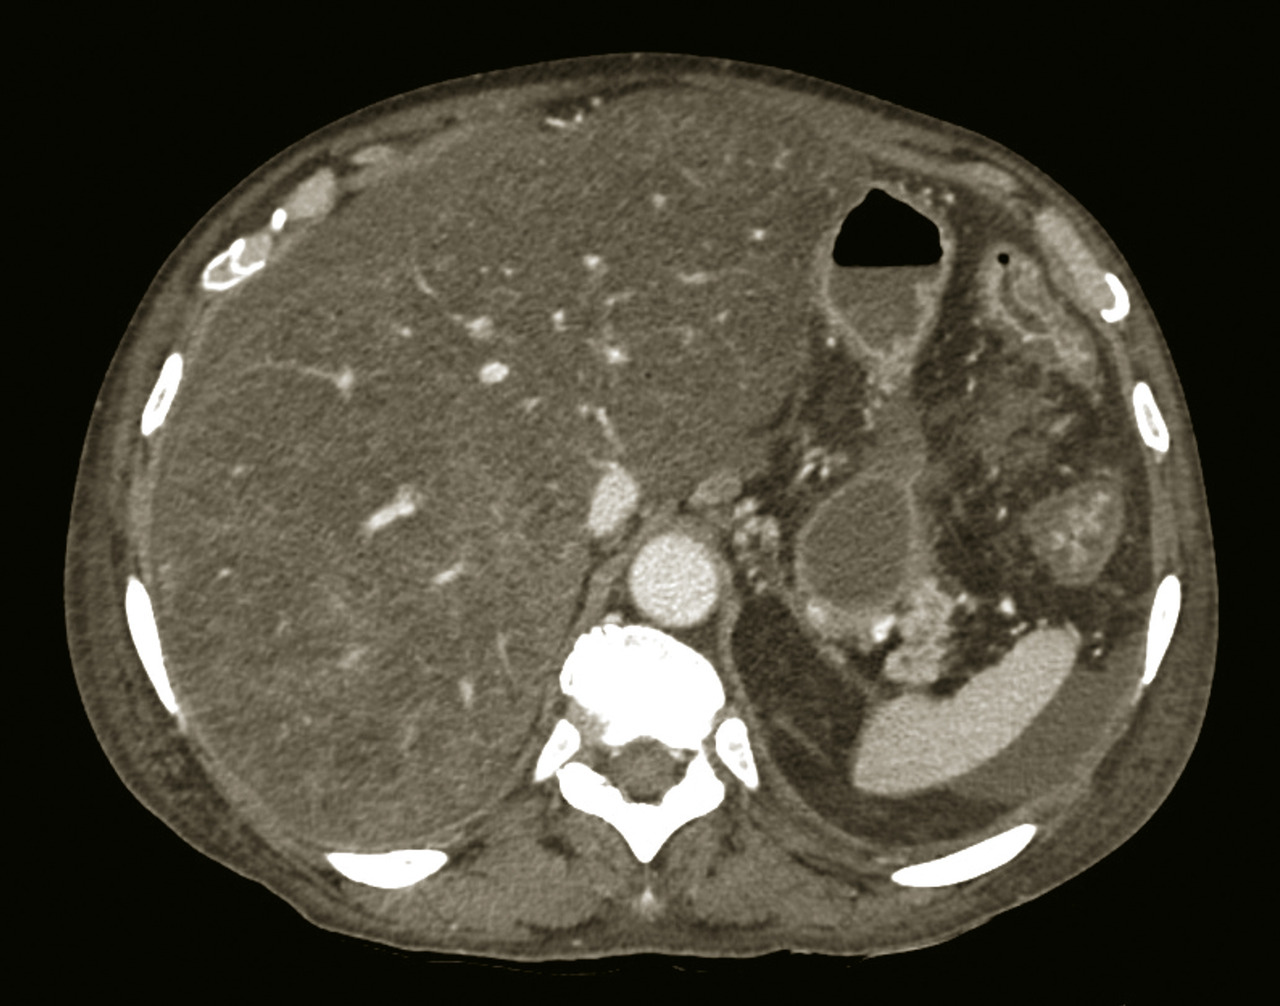

Une imagerie en coupe, tomodensitométrie (TDM) ou imagerie par résonance magnétique (IRM), avec étude triphasique (temps artériel, portal et tardif) après injection de produit de contraste, peut être utile au diagnostic étiologique d’une hépatomégalie.

◗ Donner les caractéristiques du carcinome hépatocellulaire en imagerie injectée : aspect hypervasculaire au temps artériel (phénomène de wash-in), et hypovasculaire au temps portal ou tardif (phénomène de wash-out) par rapport au parenchyme hépatique adjacent.